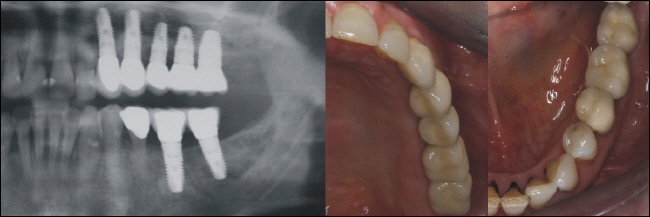

Versorgung

Jedes Implantat wird mit einer einzelnen Krone versorgt, da dadurch höchste Genauigkeit und beste Pflegemöglichkeit gewährleistet wird. Der Implantologe nennt diese Variante eine Versorgung mit Einzelzahnkronen oder auch eine „Zahn zu Zahn“ Versorgung im Gegensatz zu einer implantatgetragenen Brücke, die im Oberkiefer ebenfalls auf nur drei Implantaten theoretisch möglich wäre.

Das rechte Bild zeigt die Kronen auf dem zahntechnischen Meistermodell.